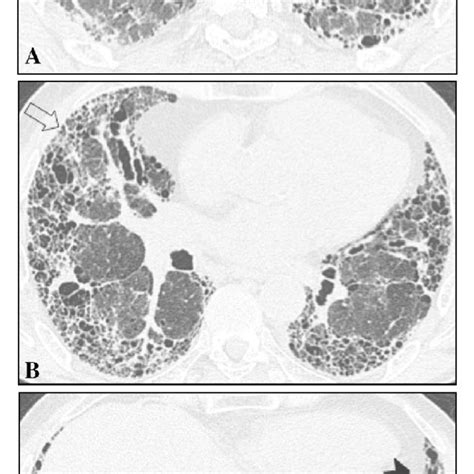

Management of malignant pleural mesothelioma - part 1 ...

Management of malignant pleural mesothelioma - part 1 ... from media.springernature.com

Combined modality treatment in mesothelioma: a systemic ...

Combined modality treatment in mesothelioma: a systemic ... from cdn.amegroups.cn